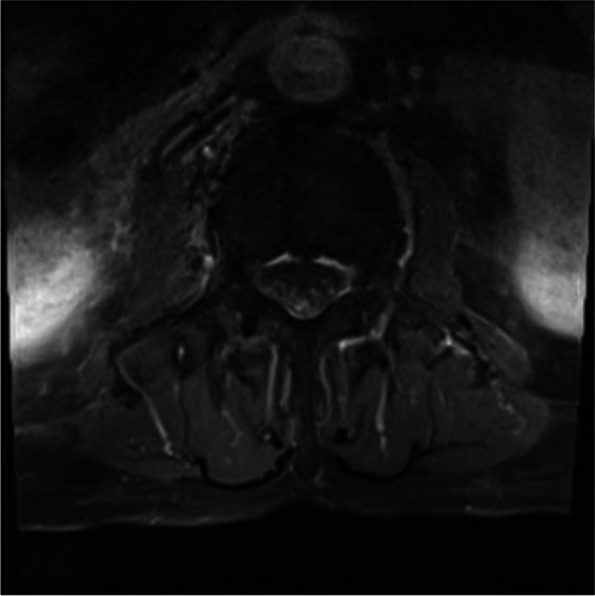

Magnetic resonance imaging (MRI) of the brain showed no abnormalities. The complete spine MRI showed central canal stenosis at C4–5 and C5–6 without significant cord compression and mild central canal stenosis at L5-S1. The gadolinium enhanced MRI revealed the enhancement along the entire lumbosacral nerve root (cauda equina) (Fig. 1). Cerebrospinal fluid (CSF) analysis was performed 1 month after the onset of symptoms (7th admission day): elevated white blood cell count (19 cells/μL: polymorphonuclear cell 25%, lymphocyte 75%) and protein level (142.5 mg/dL) were observed. Red blood cell was not present, and glucose level (70 mg/dL) was within the normal range. Bacterial culture, tuberculosis polymerase chain reaction (PCR) test, and Varicella-zoster virus IgG and IgM of the CSF were negative. However, CMV detection by PCR was positive. In the blood test, CMV detection by real time PCR showed 6.73 × 102 IU/mL and 740 copies/mL. Human immunodeficiency virus antigen, antibody, and ribonucleic acid tests were negative. Therefore, the diagnosis of lumbosacral polyradiculitis due to CMV was confirmed. Ganciclovir (250 mg twice daily) was administered intravenously.

Fig. 1.

T1-weighted gadolinium-enhanced axial MRI at L4–5 level performed 3 weeks after the onset of symptoms due to cytomegalovirus polyradiculitis showing the enhancement in the entire lumbosacral nerve root

In our patient, gadolinium-enhanced MRI showed inflammation (nerve enhancement) in multiple lumbrosacral nerve roots, which was a supportive finding in the diagnosis of CMV lumbosacral polyradiculitis. Nerve enhancement in gadolinium-enhanced MRI is related to the accumulation of gadolinium in granulation tissue, inflammatory cytokines, and disruption of endoneurial capillaries [11]. Cytokines induced by CMV infection result in the breakdown of the blood-nerve barrier and increase vascular permeability, which causes the enhancement in the nerve tissue. Other than virus infection, the enhancement of multiple nerve roots can be present in radiculitis due to bacterial infection, Guillain-Barre syndrome, and neuralgic amyotrophy [11–13].